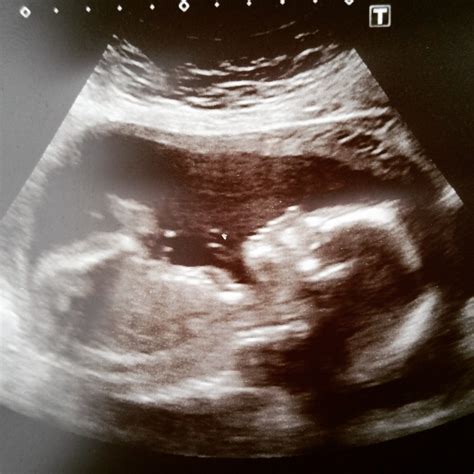

The Twenty Week Scan is a detailed ultrasound examination that provides a comprehensive view of the baby's anatomy. It is usually performed by a trained sonographer or radiologist and takes about 20-30 minutes to complete. During this scan, high-frequency sound waves are used to create images of the baby inside the womb. These images help healthcare providers evaluate the baby's growth and development.

Before the scan, you will be asked to lie down on an examination table. A gel will be applied to your abdomen to help the ultrasound probe glide smoothly and transmit sound waves. The probe will be moved across your belly to capture images from different angles. You may be asked to change positions or hold your breath briefly to get clearer images.

During the scan, the sonographer will:

• Measure the baby's head circumference, abdominal circumference, and femur length to assess growth.

• Check the baby's heart, brain, spine, kidneys, and other organs for any abnormalities.